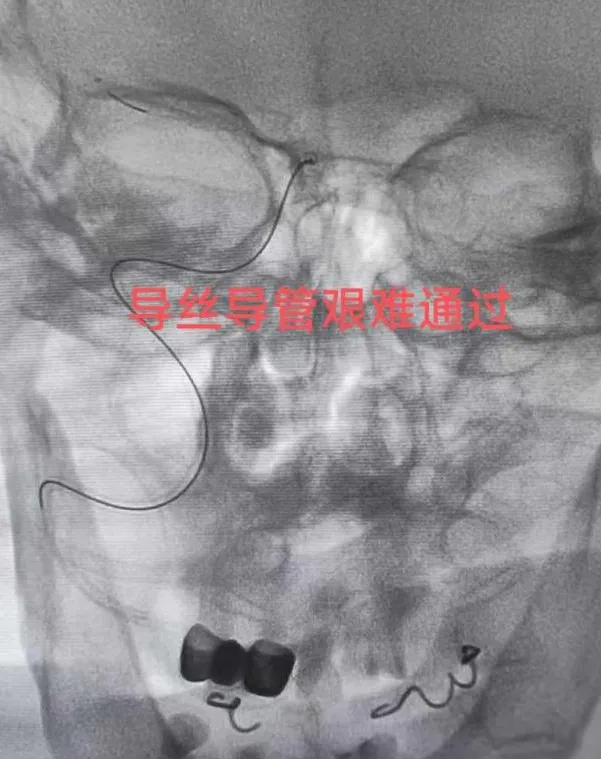

“必须立即进行脑动脉取栓手术!”神经内科王文杰主任了解患者详情后当机立断。与家属充分沟通并获得同意后,患者被迅速送入介入治疗室。术中造影显示,患者右侧大脑中动脉M1末端完全闭塞。术中造影发现患者多发动脉硬化、狭窄,血管迂曲明显,情况复杂,手术难度较高。且患者病情进展加重,王文杰、于弋水决定在局麻下为患者急诊动脉机械取栓。根据患者血管特点,选用合适导管行“血栓抽吸术”,仅一次操作即完整取出暗红色血栓,原闭塞血管血流瞬间恢复至最高分级(mTICI 3级),从穿刺到血管完全再通仅用50分钟。